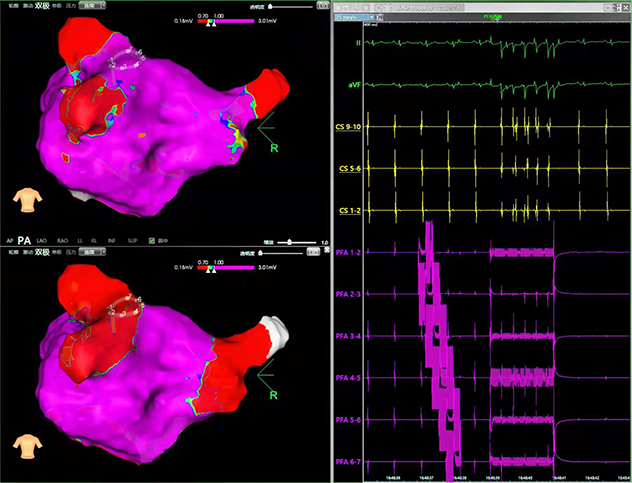

J9九游会电子LEAD-PFA脉冲电场消融系统是一款基于磁定位导航并且集三维建模、标测、消融于一体的心脏脉冲电场消融系统。不同于传统的射频、冷冻等消融技术,该系统利用脉冲电场技术实现精准消融以及快速消融。消融速度快、时间短,对导管的贴靠要求更低,显著提高了手术的效率。可以避免传统射频消融手术中的焦痂和爆裂风险,同时还能避免损伤毗邻的组织(神经、冠脉、食道等),大大提高了手术的安全性。该系统预期用于房颤消融术,可以预见会给国内房颤消融术带来变革式技术进步。

病例回顾